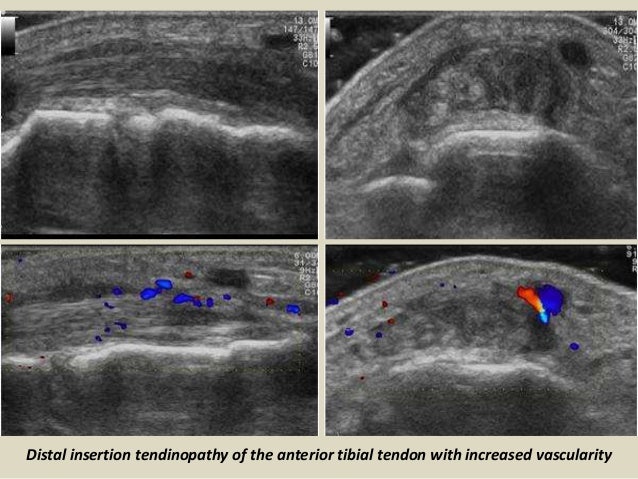

Distal insertion tendinopathy of the anterior tibial tendon with increased vascularity

34. 34. Distal insertion tendinopathy of the anterior tibial tendon with increased vascularity